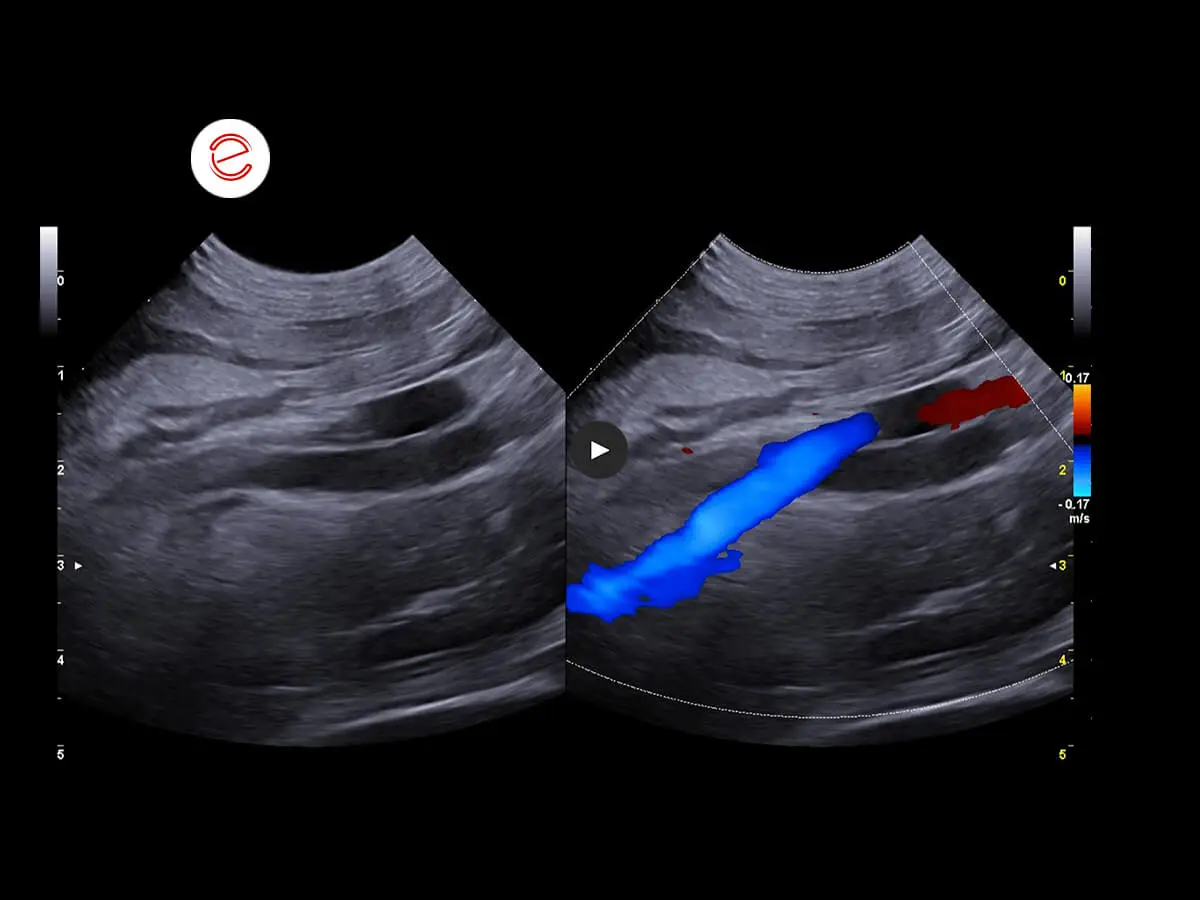

Vascularization of the right kidney preserved.

Course of the right ureter in relation to the vessels. Ureteral ectasia observed throughout its course with diffuse wall thickening.